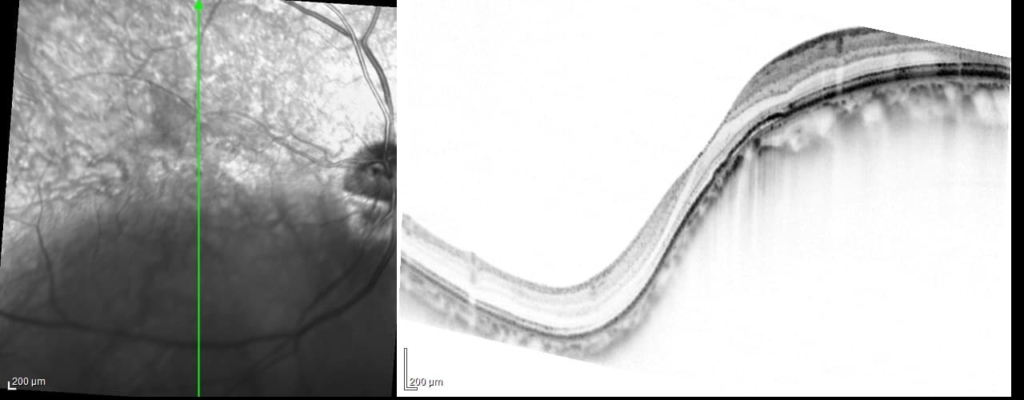

両眼ともに、後部ぶどう腫staphylomaの上縁に一致して乳頭下縁から黄斑を横断するように帯状の網脈絡膜の萎縮巣がみられる。また後部ぶどう腫領域に一致して網膜・脈絡膜が菲薄化しているため、紋理眼底tessel lated fundusがみられる。

後部ぶどう腫の上縁に漿液性網膜剥離(SRD)がみられる。この後部ぶどう腫と正常部の境界付近に脈絡膜新生血管の発生を見ることもあるため、注意が必要。